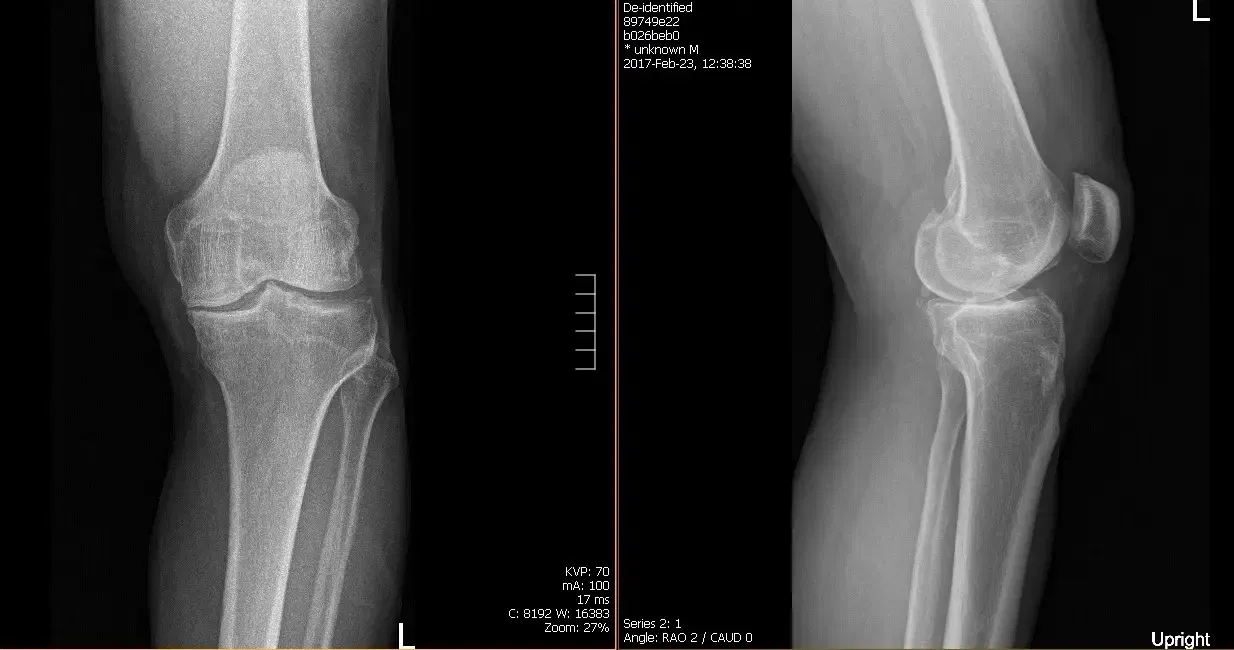

His HEP consisted of quadricep isometric, hamstring, and gluteal exercises, a seated knee flexion stretch and a supine knee hang. Patient was instructed to continue his HEP in addition to the new HEP program that would be given to him in outpatient PT. Presurgical films revealed there are moderate osteoarthritic degenerative changes.

Patient underwent a Left Total Knee Arthroplasty using custom implant, During the procedure his surgeon noted advanced osteoarthritis was already present. A medial parapatellar approach was used, the tibial resection guide was then placed into position after exposure of the tibia, and the tibial resection was made and checked.

Postoperative films revealed Distal femur, patella, proximal tibia and proximal fibula demonstrate intact cortical margins with no acute fracture. His wound was inspected, clear no signs of infection.Staples removed.